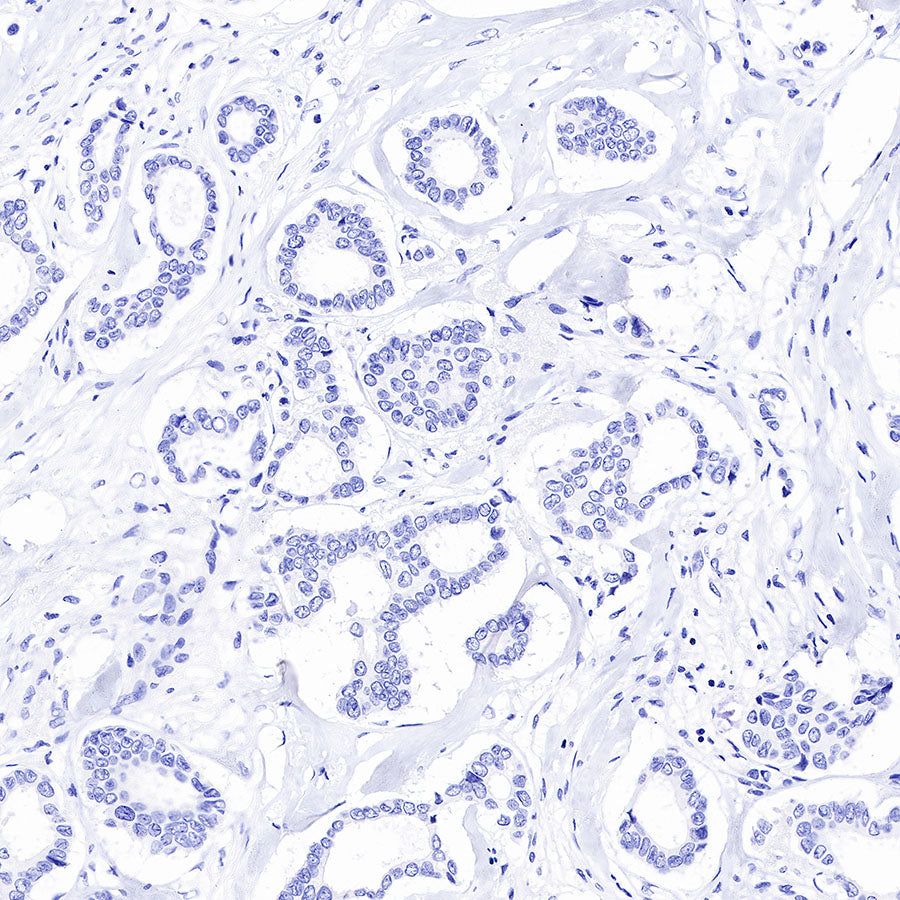

Immunohistochemistry

IHC shows positive staining in paraffin-embedded human prostatic hyperplasia. Anti-PSA antibody was used at 1/1000 dilution, followed by a HRP Polymer for Mouse & Rabbit IgG (ready to use). Counterstained with hematoxylin. Heat mediated antigen retrieval with Tris/EDTA buffer pH9.0 was performed before commencing with IHC staining protocol.